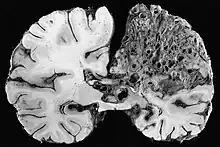

Neuropathology

Neuropathology is the study of disease of nervous system tissue, usually in the form of either surgical biopsies or sometimes whole brains in the case of autopsy. Neuropathology is a subspecialty of anatomic pathology, neurology, and neurosurgery. In many English-speaking countries, neuropathology is considered a subfield of anatomical pathology. A physician who specializes in neuropathology, usually by completing a fellowship after a residency in anatomical or general pathology, is called a neuropathologist. In day-to-day clinical practice, a neuropathologist generates diagnoses for patients. If a disease of the nervous system is suspected, and the diagnosis cannot be made by less invasive methods, a biopsy of nervous tissue is taken from the brain or spinal cord to aid in diagnosis. Biopsy is usually requested after a mass is detected by medical imaging. With autopsies, the principal work of the neuropathologist is to help in the post-mortem diagnosis of various conditions that affect the central nervous system. Biopsies can also consist of the skin. Epidermal nerve fiber density testing (ENFD) is a more recently developed neuropathology test in which a punch skin biopsy is taken to identify small fiber neuropathies by analyzing the nerve fibers of the skin. This test is becoming available in select labs as well as many universities; it replaces the traditional nerve biopsy test as less invasive.